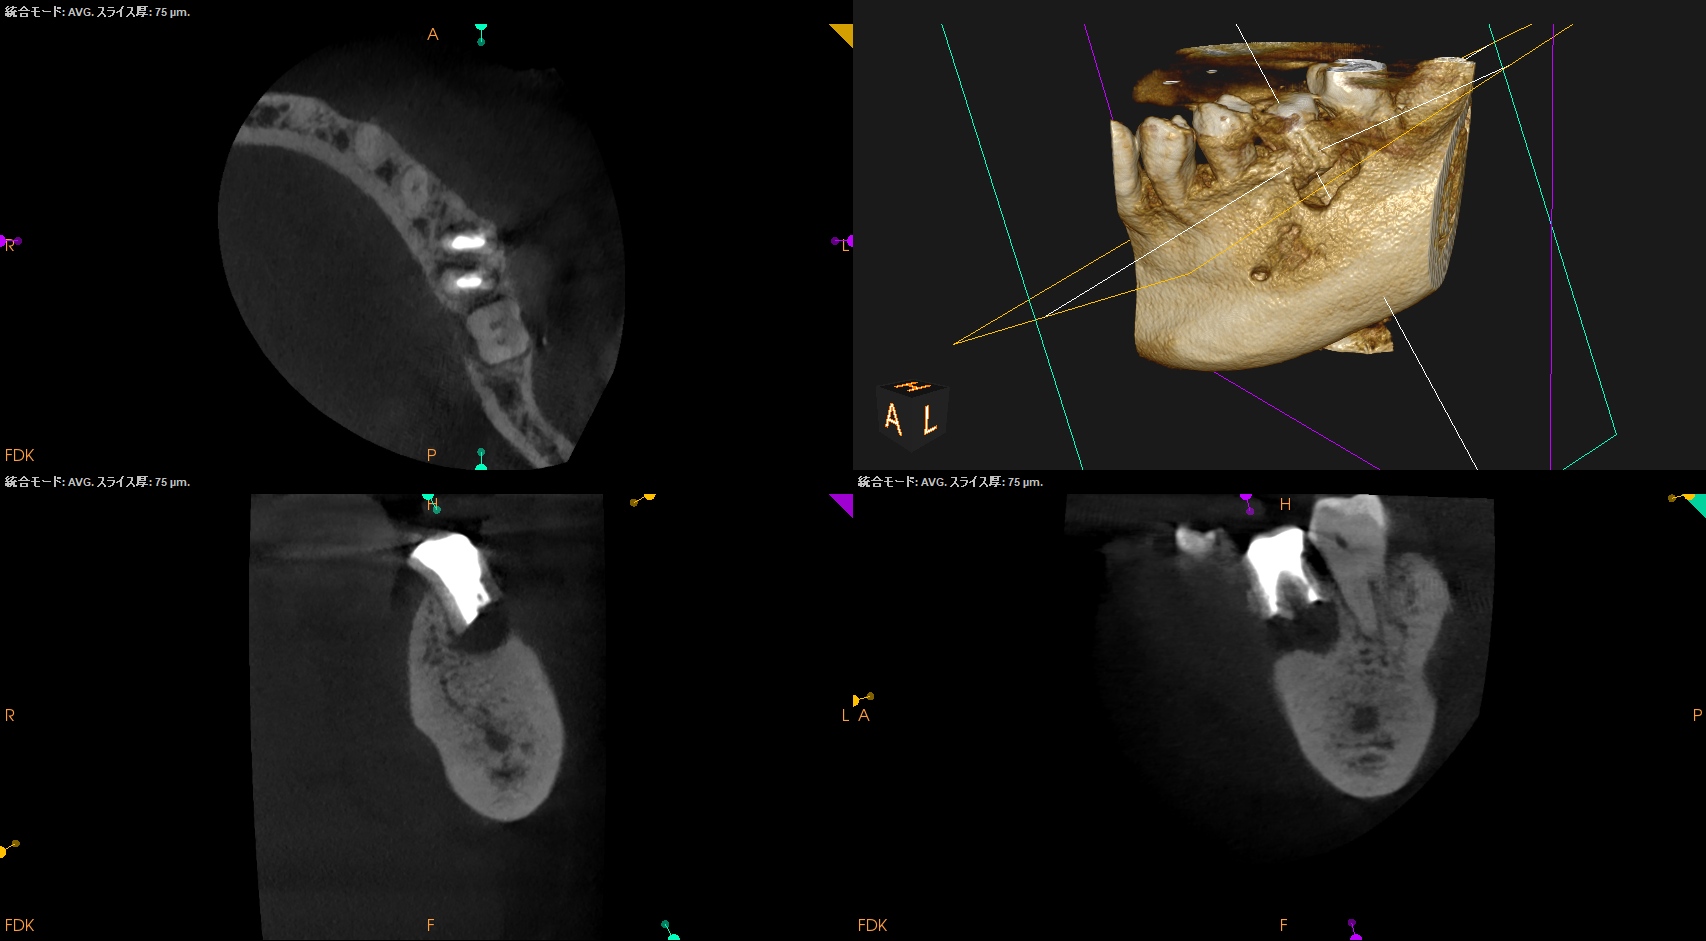

CBCT(2024.9.12)

MB

ML

D

治療はApicoectomyだ。

しかもM,Dともにである。